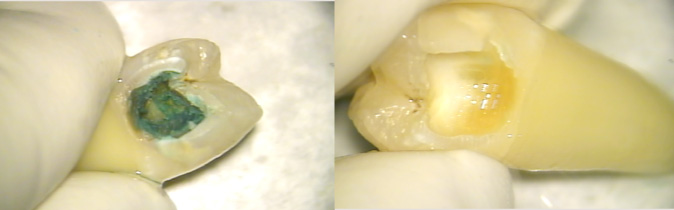

隔壁について

虫歯でラバーダムを付けられない場合このように唾液の侵入を防ぐ防波堤のようなものを作ります。これは治療中仮のふたをしますがその時に仮のふたの厚みを確保するのにも役立ちます。

根の治療はばい菌の感染との戦いです。隔壁は敵の侵入を防ぐ万里の長城のようなものです。